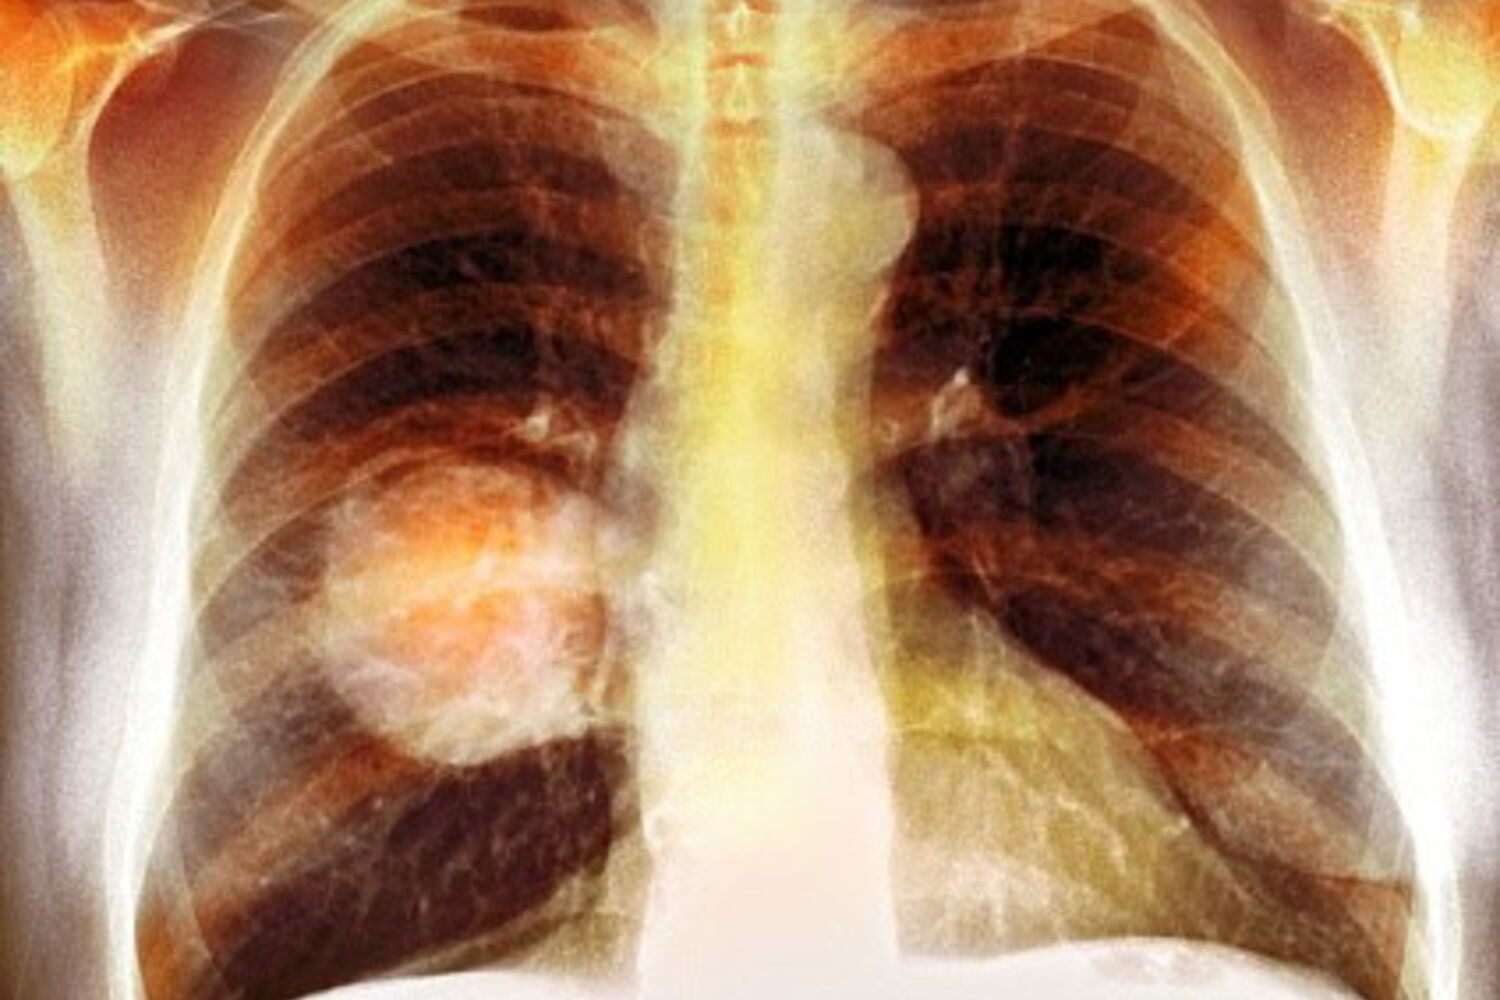

A presidente da Pulmonale criticou, esta quarta-feira, a "falta de vontade política" para implementar um rastreio nacional do cancro do pulmão, uma luta antiga da associação para reduzir a mortalidade da doença, que mata 12 pessoas por dia em Portugal.

Na véspera do Dia Mundial do Cancro do Pulmão, Isabel Magalhães realçou a importância de avançar com um programa de rastreio desta doença, que continua a ser o tumor oncológico com maior mortalidade associada, decorrente de grande parte dos diagnósticos serem feitos "numa fase muito avançada".

"Quando o diagnóstico é feito numa fase inicial, podemos ter taxas de sobrevivência até oito vezes superiores àquelas que temos quando ocorre numa fase de tardia, que é o que acontece atualmente", salientou.

Isto deve-se, entre outros motivos, ao facto de ser uma doença que na fase inicial, muitas vezes, não apresenta sintomas, ou quando apresenta, são confundidos com outras patologias, disse, salientando que o cancro do pulmão atinge maioritariamente fumadores ou ex-fumadores, que representam cerca de 85% dos diagnósticos.

Segundo o Instituto Nacional de Estatística, só em 2023, esta doença causou 4.490 mortes em Portugal, o valor mais elevado em 20 anos, o que causa em média 12 mortes por dia.